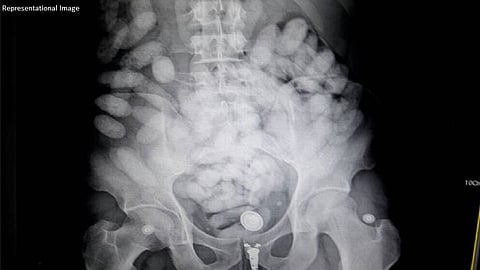

करोला लिसेट बोलीवर बेजारानो ही बोलिव्हियन तरुणी इथिओपियन एअरलाईन्सच्या विमानाने आदिस अबाबा येथून मुंबईत आली होती. एआययूला मिळालेल्या माहितीवरून मुंबईतील छत्रपती शिवाजी महाराज आंतरराष्ट्रीय विमानतळावरून शनिवारी सकाळी तिला ताब्यात घेण्यात आले. तिच्या पोटात कोकेन असल्याचा संशय अधिकाऱ्यांना होता या महिलेवर वैद्यकीय चाचणी करण्यासाठी शनिवारी न्यायालयाकडे अर्ज करण्यात आला होता. त्यानुसार जे.जे. रुग्णालयात तिचा एक्सरे व सोनोग्राफी करण्यात आली. त्यावेळी त्या पोटात संशयीत कॅप्सूल असल्याचे निष्पन्न झाले होते. त्यानंतर डॉक्टरांनी तिच्या पोटातून या 72 कॅप्सूल काढल्या. त्यात कोकेन असल्याचे निष्पन्न झाले.

जप्त करण्यात आलेल्या कोकेनचे वजन 715 ग्रॅम असून त्याची किंमत दोन कोटी 14 लाख रुपये आहे. या सर्व प्रकरणामागे सांताक्रुज येथे राहणाऱया बोलीवियातील नागरीकाचा सहभाग आहे.त्यानेच तिला पोटात कॅप्सूल लपवून प्रवास कसा करायचा, हे शिकवले होते. तस्करी करून आणलेले ड्रग्सही तिला त्याच व्यक्तीचा द्यायचे होते. तिचा तिकीटखर्चही आरोपीने केला होता. याप्रकरणामागे मोठी आंतरराष्ट्रीय टोळी असल्याचा पोलिसांना संशय आहे. त्याचे तार अमेरिकेपर्यत पोहोचले आहेत. यापूर्वी या महिलेने अशा पद्धतीने भारतात ड्रग्स आणले का, याबाबत अधिक तपास सुरू आहे.